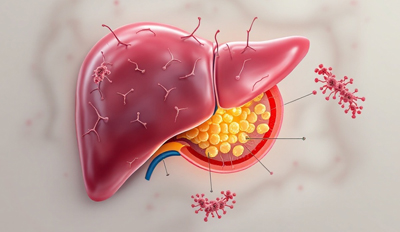

Laparoscopic surgery is a minimally invasive technique performed through small incisions using a camera, resulting in less pain, smaller scars, and faster recovery.